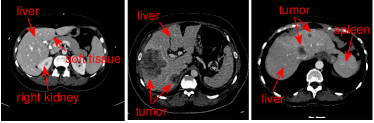

Figure 2: Flowchart of the proposed liver segmentation method

A flowchart of the proposed method is depicted in Fig. 2. The proposed method consists of two main parts: 3D deep CNNs based liver detection and 3D graph cut based segmentation refinement.